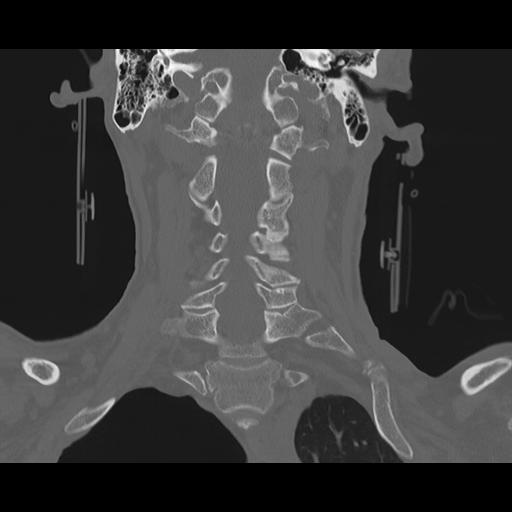

16 HUESO,,Coronal,2.000,HUESO,Coronal,